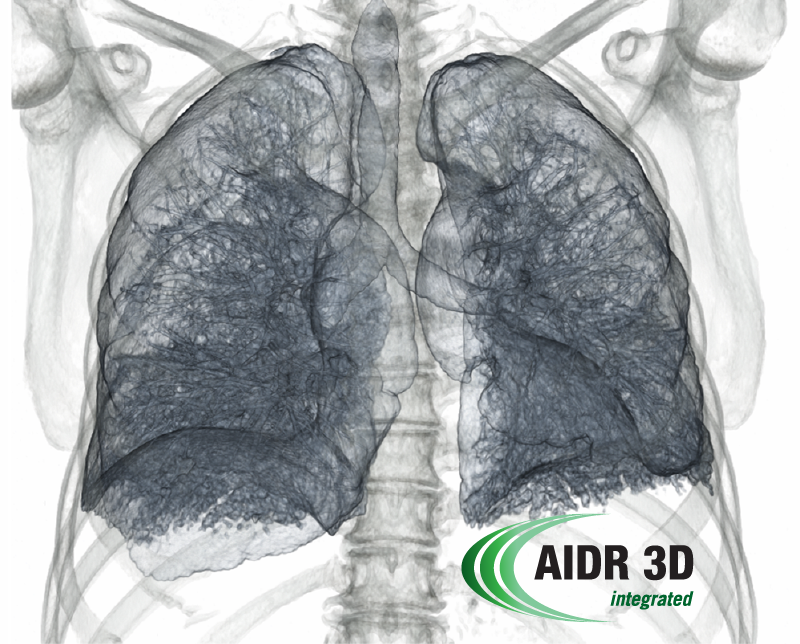

Integrated Dose Reduction That Works

Canon Medical Systems' 4th generation dose reduction, AIDR 3D Enhanced, offers superb image quality. AIDR 3D enhanced simplifies dose reduction by adaptively targeting noise in the raw data and image data space. The amount of noise reduction is optimized for the clinical task and personalized for each patient.